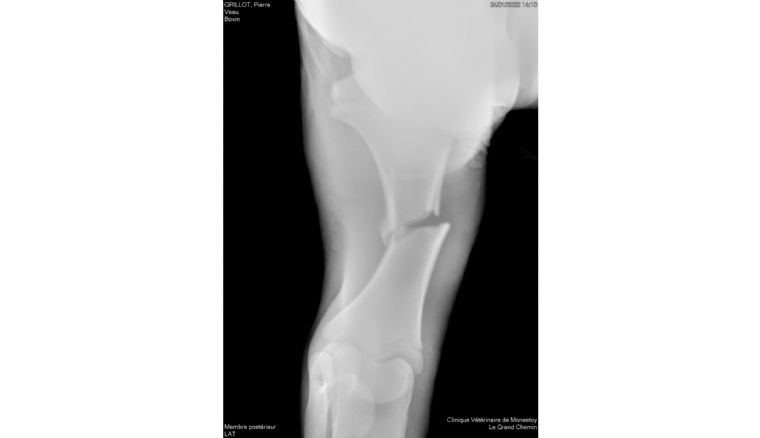

Photo n° 1 : Une fracture du tibia est diagnostiquée à la radio.

Le cas d'un très jeune veau charolais victime d'une fracture du tibia implique de réfléchir à la technique chirurgicale à mettre en oeuvre pour la correction. Les fixateurs externes sont techniquement la meilleure solution.